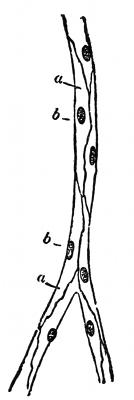

Fig. 3—Lymphatics of the head and neck.

The Lymphatics.

—The lymphatics occur in all parts

of the body, and in many respects resemble the veins,

one of the most striking similarities being that the lymphatics

contain valves just the same as the venous system.

The lymphatic capillaries are arranged in the form of

a net work and resemble closely in structure the blood

[45]

capillaries. These capillaries then unite to form the

lymph vessels and these then convey the lymph to the

subclavian veins. The lymph is a colorless fluid and

contains numerous blood corpuscles known as lymphocytes.

But in those lymphatic vessels, which have their

origin in the walls of the small intestines, the lymph,

especially during digestion, contains a great amount of

fat, so that it has a milky appearance, and for this reason

the lymphatics of this region, have been termed lacteals.

There are two main lymphatic trunks, the one on the left

side is called the thoracic duct. This duct extends from

the lower border of the second lumbar vertebra, through

the entire length of the thorax, and opens into the left

[46]

subclavian vein, close to the point where it is joined to

the left internal jugular. It receives the lymph from the

lower limbs, the pelvic walls and

viscera, the abdominal walls and

viscera; the lower part of the

right half and the whole of the

left half of the thoracic viscera,

the left side of the neck and head

and the left arm.

Fig. 4—Lymphatics of

the leg.

The other duct is called the

right lymphatic duct and receives

lymph from the upper part of

the right side of the thoracic wall,

part of the right side of the diaphragm

and the right lobe of the

liver, the whole of the right arm

and neck and right side of the

head. This trunk is very short

and empties its supply of lymph

into the right subclavian vein.

Receptaculum chyli is the expanded

portion of the thoracic

duct just at its beginning. Its

function is to receive the lacteals

which come from the villi of the

intestines.

Lymph glands are the enlargements

of the lymph vessels. They

occur frequently in the lymphatic

system, being most numerous in

[47]

the axillary space, the cervical region (in the neck)

and in Scarpa's triangle.

The lymphatic system aids greatly in warding off such

diseases as blood poisoning, anthrax, etc.

The lacteals are the lymphatics which carry the

chyme from the villi of the intestines and deposit it in

the receptaculum chyli.